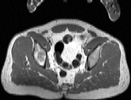

Visible Human male: Sectio transversalis 1844

NMR

Pd                          / T2 \                         T1